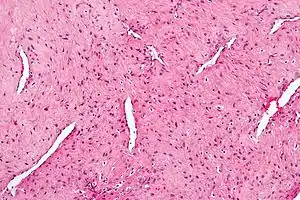

Micrograph of a nasopharyngeal angiofibroma H&E stain.